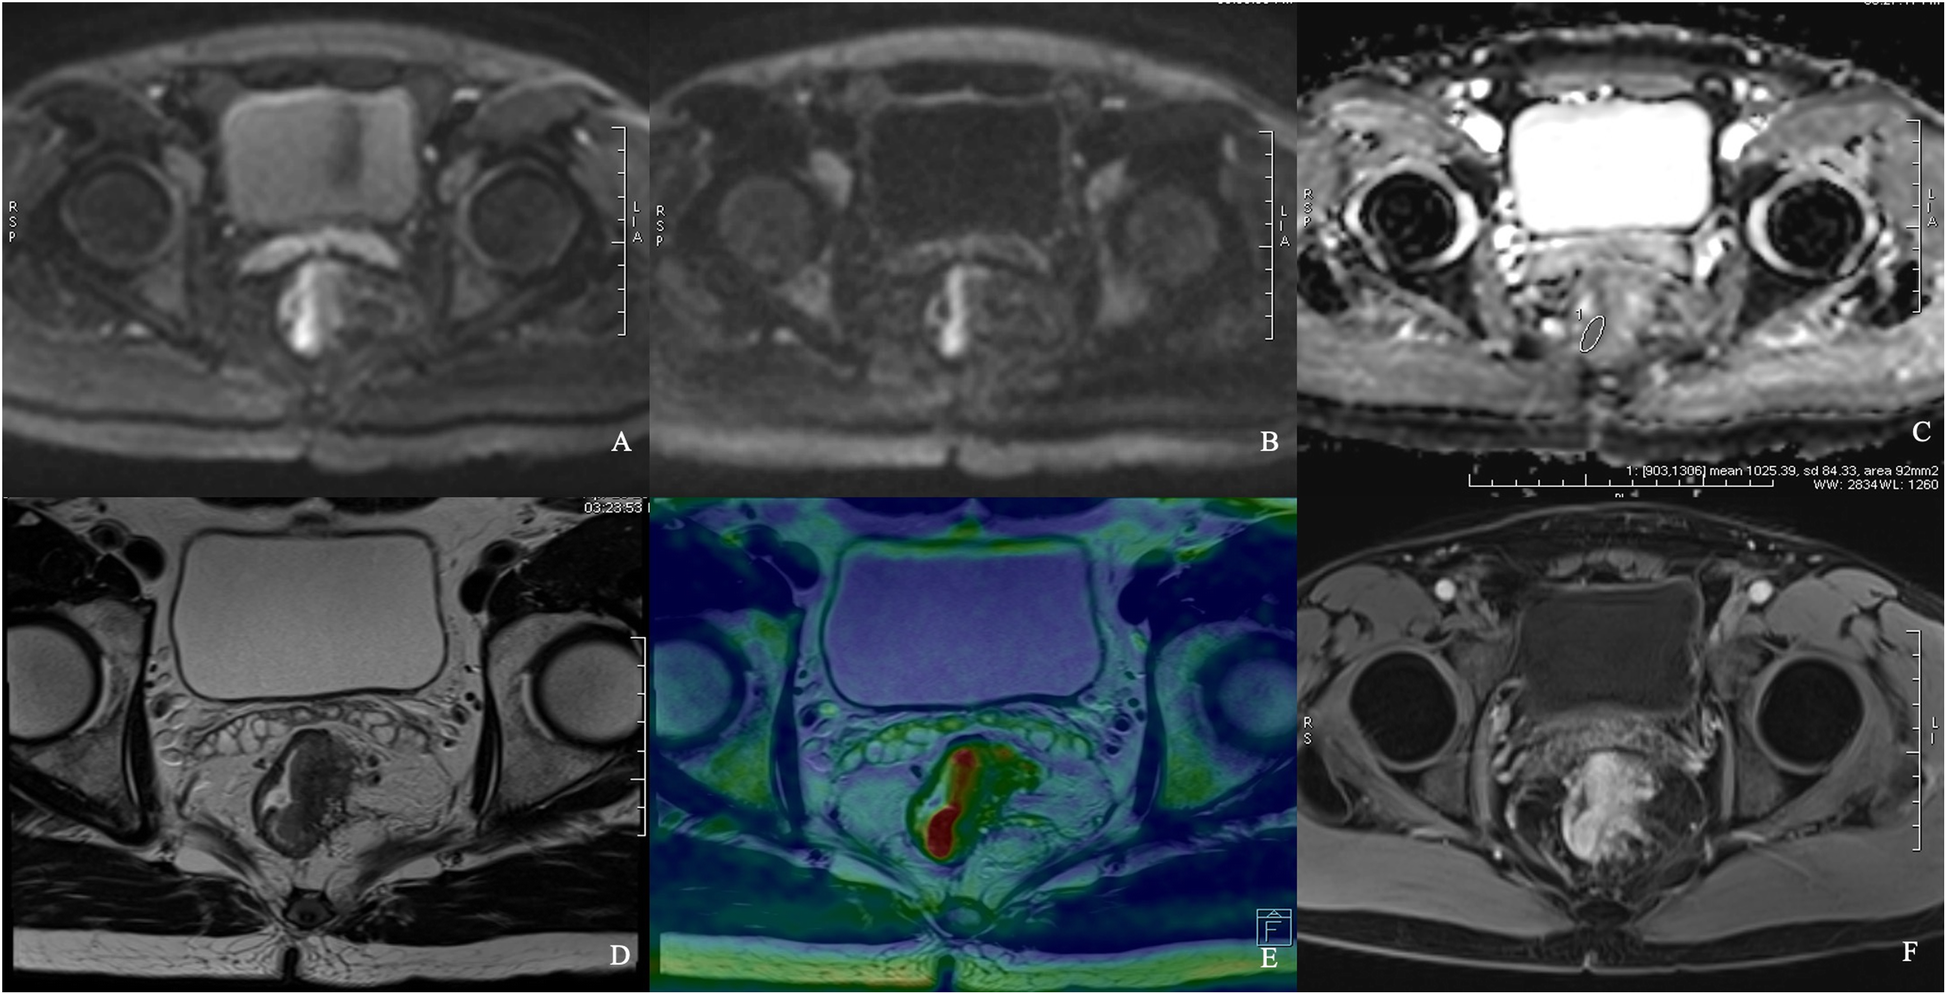

Fig. 6 | Cancer Imaging